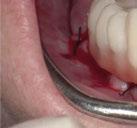

Figuras 1-3.

La niña de las figuras 1 a 3 presenta una leve asimetría facial con patrón braquifacial por tercio inferior disminuido y mentón desviado ligeramente hacia la derecha; los labios son competentes y en sonrisa apenas se exponen los incisivos. El perfil es excesivamente convexo,

Figuras 4-8.

La exploración intraoral (figuras 4 a 8) revela una Clase II molar y canina completa, líneas 1/2 dentarias superior 0,5 mm e inferior 1 mm ambas desviadas hacia la derecha, los incisivos superiores excesivamente protruidos y vestibulizados (seguramente debido a la interposición del labio inferior), resalte de 13 mm y sobremordida 2/3 de corona. La discrepancia oseodentaria

inferior es de -3,5 mm y la curva de Spee de 4 mm.